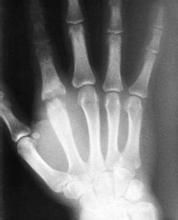

2.X線檢查

早期表現為關節囊積液擴張,如髖關節則會有股骨頭向外移位甚至脫出。感染持續存在,可看到骨脫鈣和關節間隙變窄。